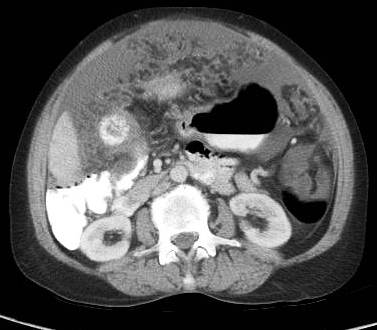

Ascites in advanced gastric cancer swollen stomach cancer. Ascites caused by cancer is called malignant ascites. We'll focus this article on malignant ascites in advanced gastric cancer or swollen stomach cancer. 4 stomach cancer symptoms. Our doctors are here to help you make sense of your stomach cancer.